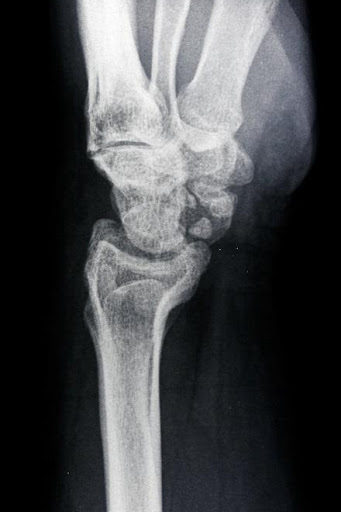

Skafolunat bağ yaralanmaları en sık görülen el bileği yaralanmalarıdır. Bu bağ skafoid ve lunat kemiği bir arada tutar. Bu bağın bozulması skafolunat instabilitesine neden olur. Geç aşamalarda skafoid ve lunat kemik arasında bir boşluk oluşur ve skafolunat ayrışması olarak bilinir.

Skafolunat ekleminin ayrıldığını gösteren bileğin stresli görünümü